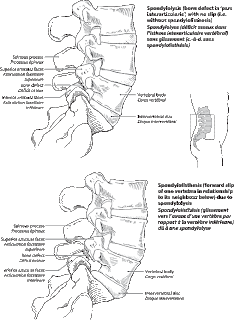

I had a "tube" MRI a few years ago that came back with a diagnosis of a spondylolisthesis. You will notice that with this new "Open" MRI that I am not diagnosed with that anymore which is a good thing. Unfortunately, I'm still dealing with the pain, but hey, life goes on and you'd be lucky to ever hear me complain when I'm out riding unless it's really bad.

L5-S1: The intervertebral disc is normal in morphology and signal characteristics. No evidence of disc herniation or bulge. There is bilateral spondylolysis of L5. There is no evidence of spondyloisthesis. No subluxation in the standing position. Moderate bilateral neuroforaminal stenosis.

Mild degenerative disc disease as described. Spondylolysis of L5 without evidence of spondylolisthesis.